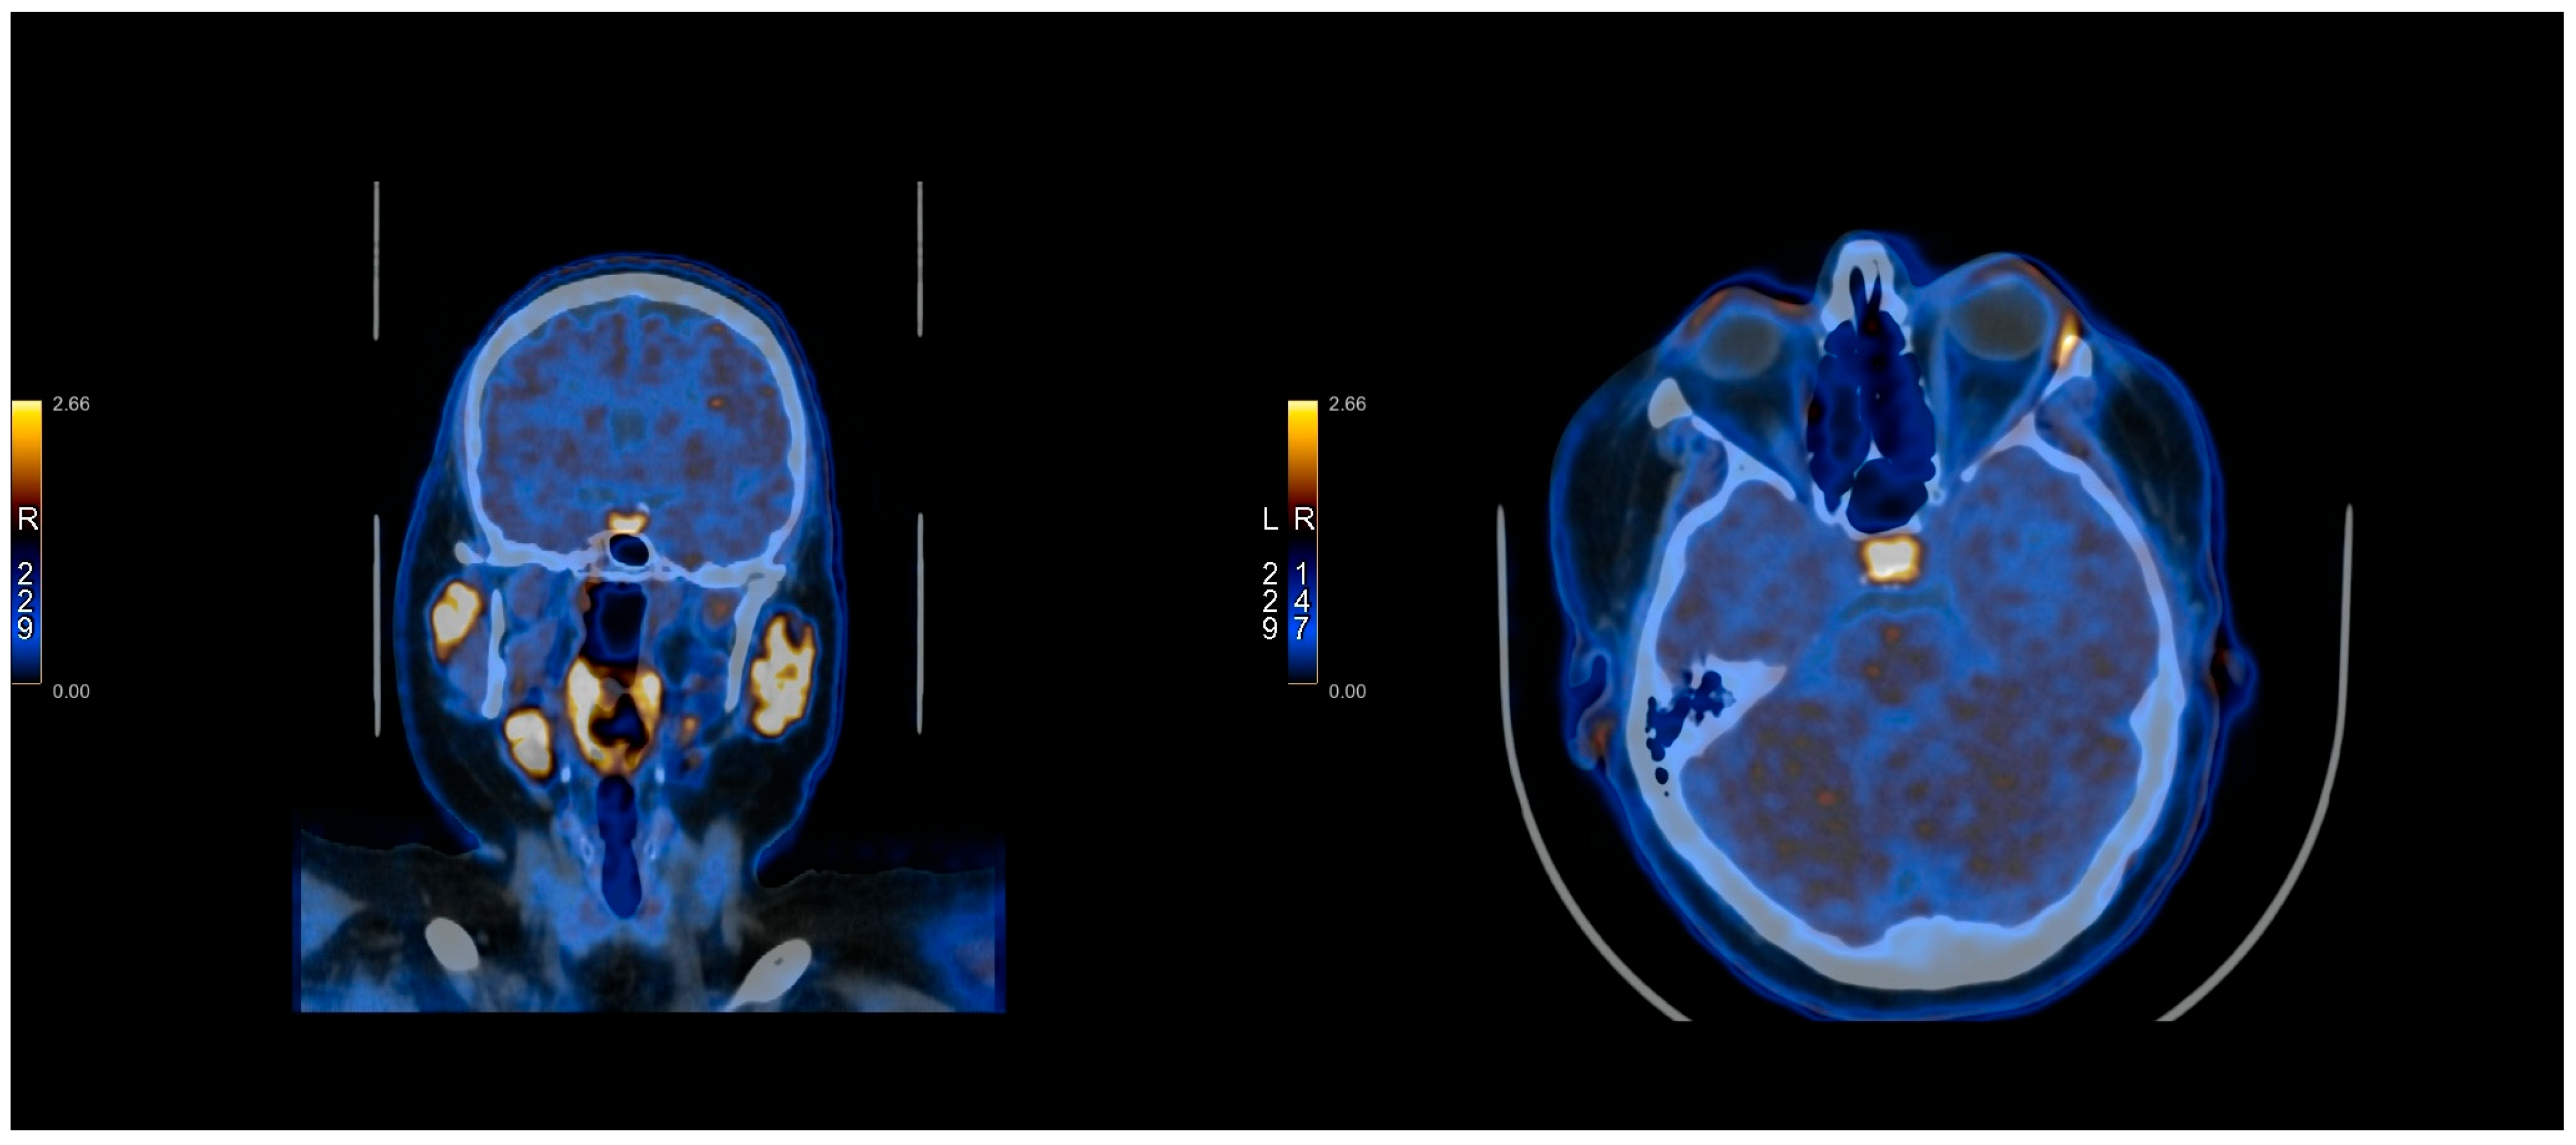

2.3. PET Protocol

2.4. Methionine Protocol